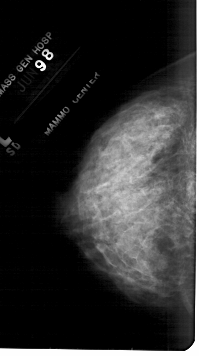

A_1845_1.RIGHT_MLO

RIGHT_MLO LINES 5491 PIXELS_PER_LINE 2941 BITS_PER_PIXEL 12 RESOLUTION 43.5 OVERLAY